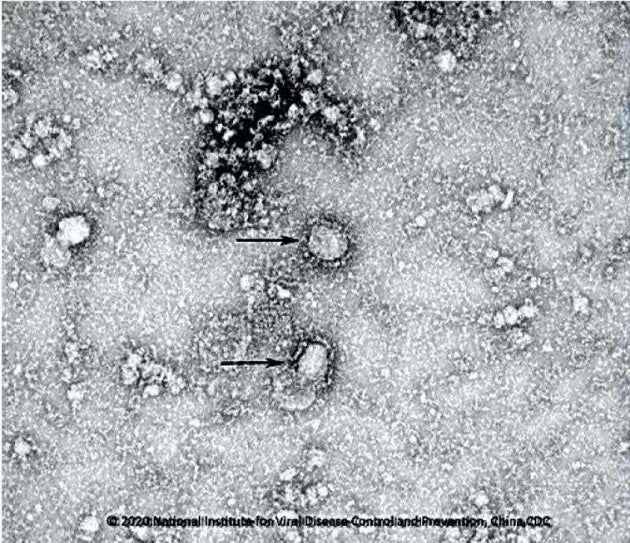

Κίνα: Στη δημοσιότητα οι πρώτες εικόνες του φονικού κοροναϊού

Οι πρώτες εικόνες του θανατηφόρου κοροναϊού, από τον οποίον έχουν χάσει τη ζωή τους τουλάχιστον 25 άτομα και έχουν μολυνθεί περίπου άλλα 830 στην Κίνα και σε άλλες χώρες, δόθηκαν στη δημοσιότητα την Παρασκευή.

Το Ινστιτούτο Μικροβιολογίας της Κινεζικής Ακαδημίας Επιστημών κοινοποίησε τις φωτογραφίες, καθώς οι αρχές έχουν βάλει σε καραντίνα 10 πόλεις και πάνω από 30 εκατ. κατοίκους στην επαρχία Χουμπέι.